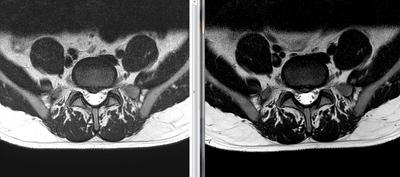

Not, i've done a NEW MRI (in the left is the MRI made in january, and in the right image is the MRI made in february 2016). The first was in january 2016, and this is february 2016.

The main difference in imaging is that the HDL got a little bigger, and also got to the point where the disc material got out and is "leaking" near the S1 right nerve root slightly compressing it.